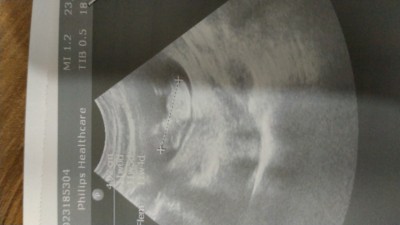

Bir bakar mısınız cinsiyetle ilgili sizce nedir güzel anneler

Gebelik haftası 11